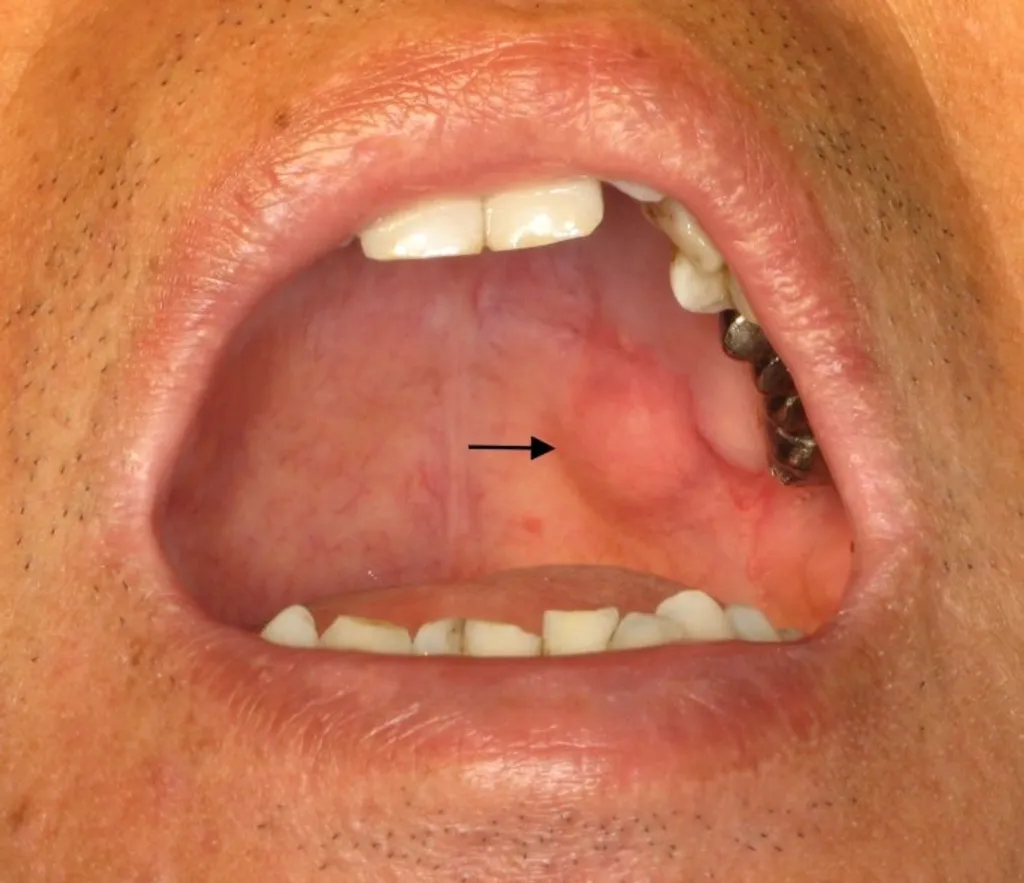

നാവിന്റെ താഴെ വായുടെ അടിത്തട്ടിൽ എല്ലിനോടുചേർന്ന ഭാഗത്താണ് ഇവ കാണപ്പെടുന്നത്. ഇതിന്റെ നാളികൾ (Bartholins duct), സബ്മാൻഡിബുലാർ നാളിയുമായി (Submandibuct ducts) ചേർന്ന് പ്രവർത്തിക്കുന്നു. ഉറങ്ങുമ്പോഴും വായിലെ ഈർപ്പം നിലനിർത്തുന്നു. ഈ ഗ്രന്ഥികളും മറ്റ് ലഘു ഉമിനീർ ഗ്രന്ഥികളെ (minor salivary glands) പോലെ മുഴകൾ (tumour) ഉണ്ടാകുന്ന ഗ്രന്ഥികളാണ്. ഇതിൽ ഭൂരിഭാഗവും ക്യാൻസർ വിഭാഗത്തിൽ പെടുന്നവയായിരിക്കും.

പരോട്ടിഡ് ഗ്രന്ഥികളിൽ ക്യാൻസർബാധ മറ്റു ഗ്രന്ഥികളെ അപേക്ഷിച്ച് കുറവാണ്. ഏകദേശം 20% മാത്രം. SM ഗ്രന്ഥികളിൽ 50% ഉം മൈനർ ഗ്രന്ഥികളിൽ 80 ശതമാനവുമാണ് സാധ്യതകൾ. തലയിലും കഴുത്തിലുമുണ്ടാകുന്ന അർബുദങ്ങളിൽ ആറു ശതമാനത്തോളം മാത്രമാണ് ഉമിനീർ ഗ്രന്ഥികളെ ബാധിക്കുന്നത്.

മ്യൂക്കോ എപ്പിഡെർമോയ്ഡ് ക്യാൻസർ (Mucoepidermoid cancer )ആണ് ഏറ്റവും കൂടുതലായി കാണപ്പെടുന്നത്.

അഡിനോയ്ഡ് സിസ്റ്റിക് കാർസിനോമ (Adenoid cystic carcinoma) ഞരമ്പുകളിലൂടെ പടർന്ന് വേഗം വ്യാപിക്കുന്നതിനാൽ മാരകമായ ക്യാൻസർ ആണ്. സ്ക്വാമസ് സെൽ കാർസിനോമ ( squamon cell carcinoma), അഡിനോ കാർസിനോമ (adeno carcinama) മുതലായവയും കാണപ്പെടുന്നു.

വളരെ അപൂർവമായി മറ്റു അവയവങ്ങളിൽ ഉണ്ടാകുന്ന ക്യാൻസറുകൾ, ഉദാ: വായിലെ ക്യാൻസർ, അസ്ഥി കാൻസർ (bone cancer), ചെവിയിലെ ക്യാൻസറുകൾ എന്നിവ പടർന്ന് ഉമിനീർ ഗ്രന്ഥികളിലേക്ക് ബാധിക്കാം.

പരോട്ടിഡ് ഗ്രന്ഥിയിലുണ്ടാവുന്ന പ്രധാന ക്യാൻസർ ആണിത്. ഇത് വീര്യം കുറഞ്ഞതും പക്ഷേവളരെ വേഗത്തിൽ പടരുന്നതുമായ രണ്ടിനങ്ങളായാണ് ഉമിനീർഗ്രന്ഥിയിൽ ഉണ്ടാകുന്നത്. വേഗം പടരുന്ന തരത്തിലുണ്ടാകുന്നത് രോഗി മരിക്കുന്നതിന് കാരണമാകുന്നു.

ക്യാൻസറുകൾ പൊതുവെ വളരെവേഗം വലുതാവുന്നു. ട്യൂമറുകൾ കല്ലുപോലെ കട്ടിയായിട്ടാണ് സ്പർശിക്കുമ്പോൾ മനസിലാകുക. മസിലിലും താടിയെല്ലിലും മുഖത്തെ ചർമത്തിലും ട്യൂമർ അതിവേഗം ഒട്ടിപ്പിടിക്കുന്നു. മുഖത്തിന്റെ ചർമ്മവും അഴുകി വ്രണമായി തീരുന്നു. ഫേഷ്യൽ നാഡിയുടെ (Facial nerve ) പ്രവർത്തനം നിലയ്ക്കുകയും കണ്ണുകൾ അടയ്ക്കുവാൻ സാധിക്കാതെ വരികയും, വായുടെ കോണുകൾ കോടിപ്പോകുവാൻ ഇടയാകുകയും ചെയ്യുന്നു. കഴുത്തിലുള്ള കഴലകൾ വീർക്കുകയും മറ്റ് ആന്തരാവയവങ്ങൾ ക്യാൻസർ സംക്രമണംവഴി വ്യാപിക്കുകയും രോഗി മരണത്തോടടുക്കുകയും ചെയ്യുന്നു.